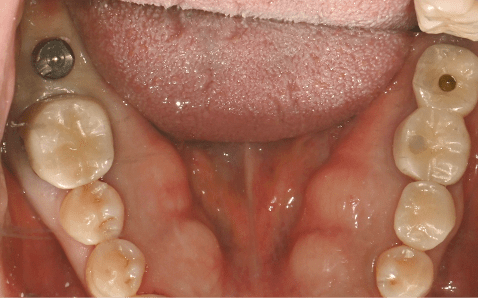

Case 02

임플란트 식립 전 절개없는 임플란트 식립 직후

촬영시기 : 2024.06.19